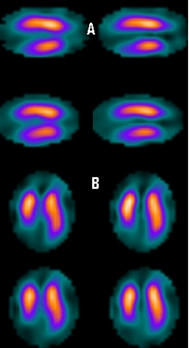

La adquisición de imágenes se realizó entre 30 y 45 minutos posterior a la inyección, con una gammacámara de doble cabezal (Siemens ECAM, Hoffman Estates, EEUU) equipada con colimadores de baja energía alta resolución, utilizando 32 imágenes por detector, matriz 64x64 y zoom de 1,45, sin corrección de atenuación. Para el estudio en reposo realizado aproximadamente 2 h 30 min más tarde, se inyectaron 25 mCi (925 MBq) de 99mTc-tetrofosmina, con adquisición en modo gSPECT de 8 imágenes por ciclo cardiaco usando ventana de tolerancia de 20%. Se procedió a la reconstrucción tomográfica con retroproyección filtrada (filtro Butterworth orden 5, frecuencia de corte 0,5 Nyquist) para el estudio gSPECT y con reconstrucción iterativa (4 Iteraciones, 8 subgrupos) para los estudios de perfusión no gatillados, reorientando los ejes del corazón para generar los cortes coronales (eje corto), sagitales (eje largo vertical) y axiales (eje largo horizontal). La valoración semicuantitativa de la perfusión y el análisis automático de la FEVI y demás valores funcionales se realizó mediante mediante un software dedicado (QPS-QGS, Cedars-Sinai, Los Angeles, EEUU). La valoración de la extensión de los defectos se realizó en base al mapa de 17 segmentos (7) (figs. 1-3).